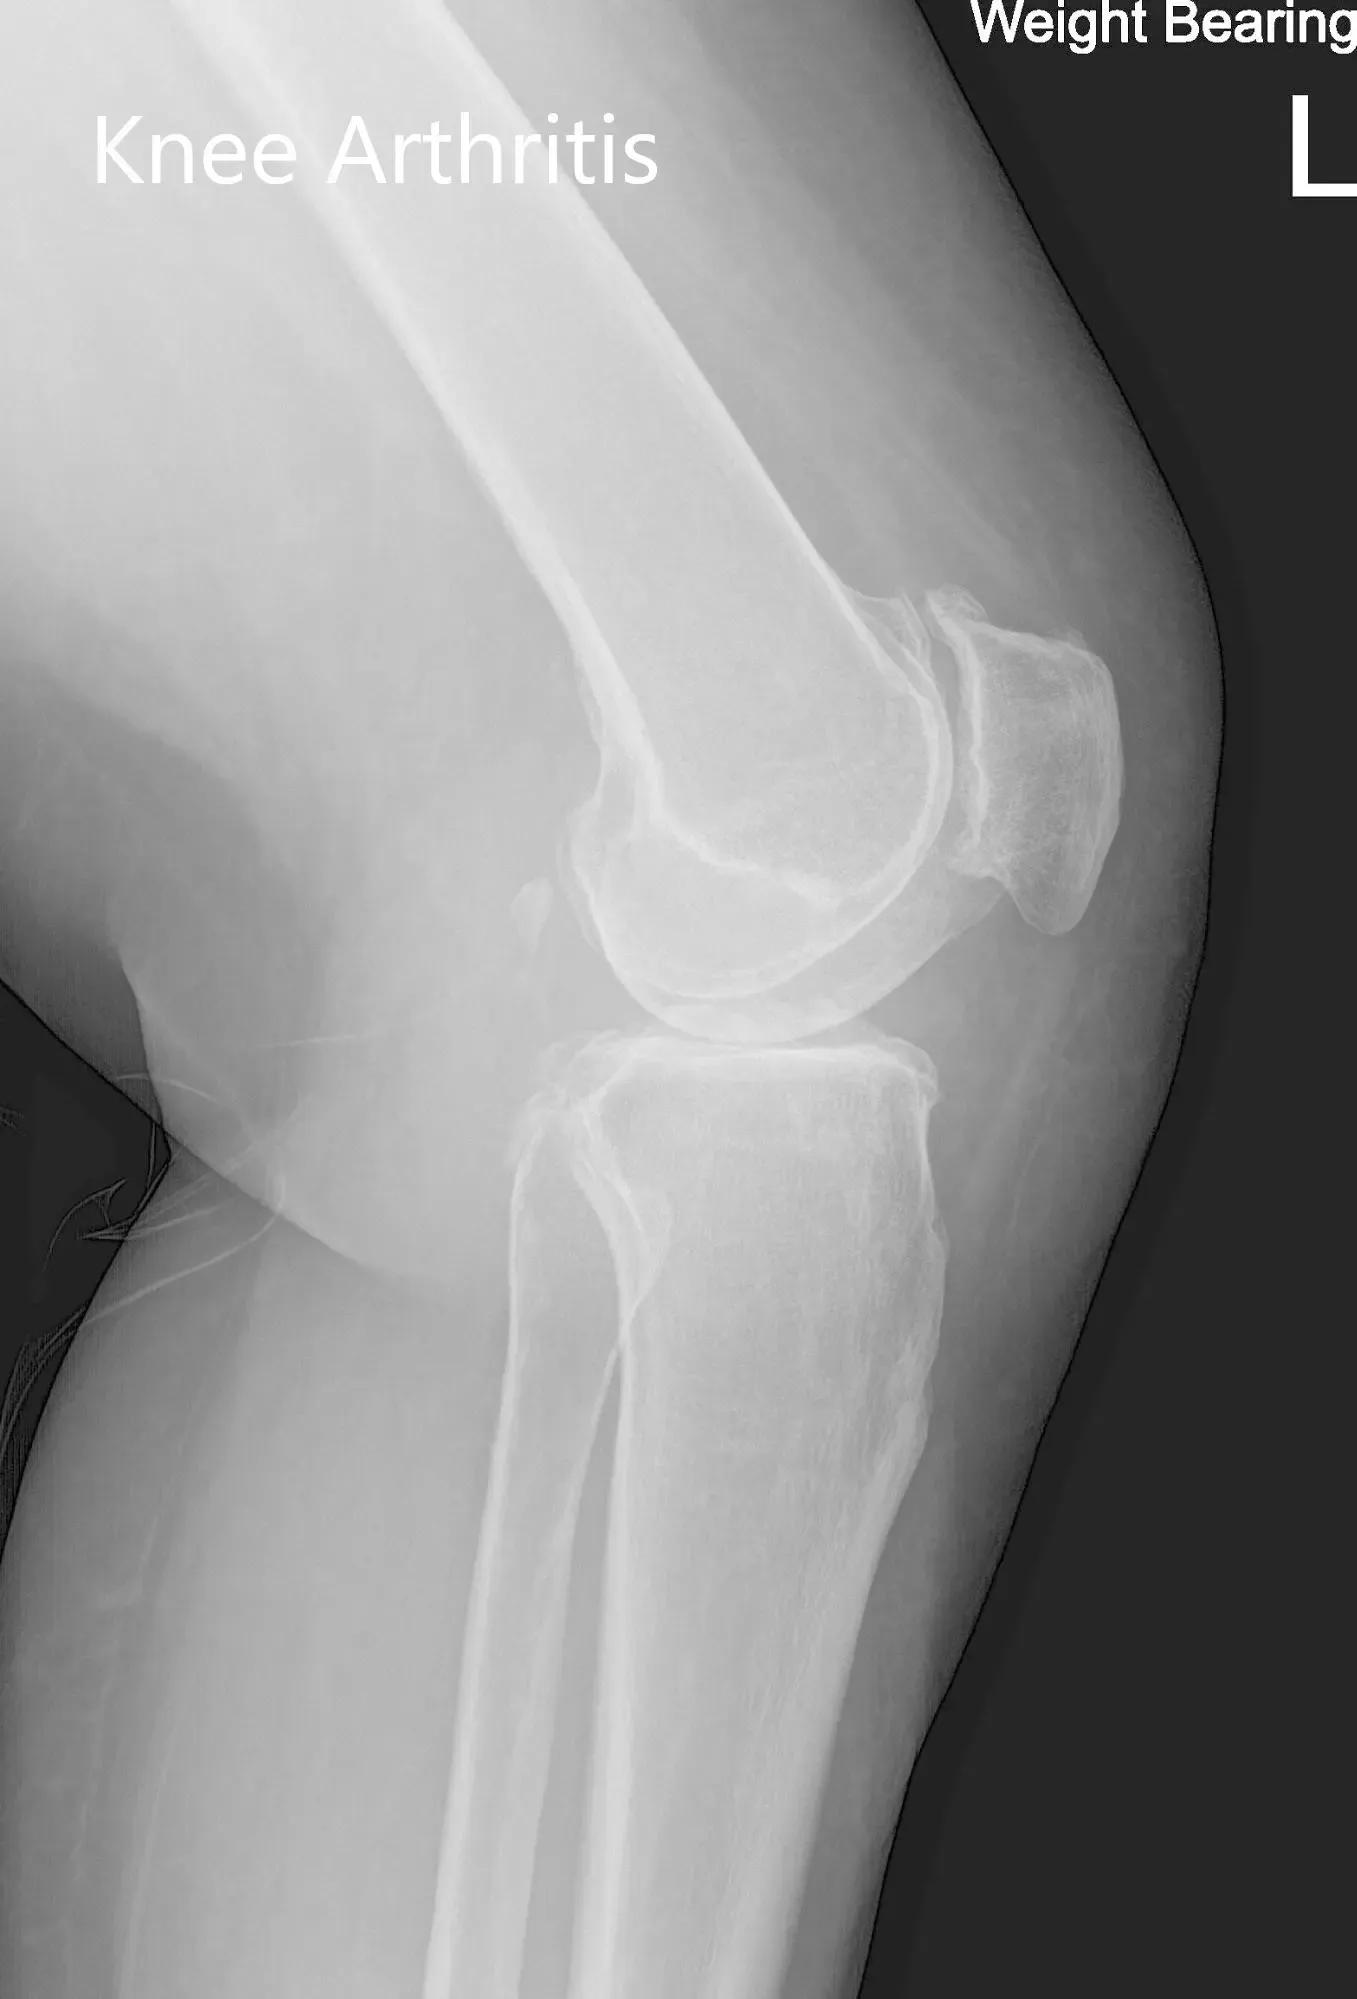

His imaging studies revealed osteoarthritic changes in the left knee. After careful consideration of lifestyle limiting knee pain and his medical condition, he was advised a custom left knee total replacement. Risks, benefits and alternatives were discussed at length with him. He was motivated to get back to his daily routine without knee pain.

Preoperative X-ray of the left knee showing AP and lateral views